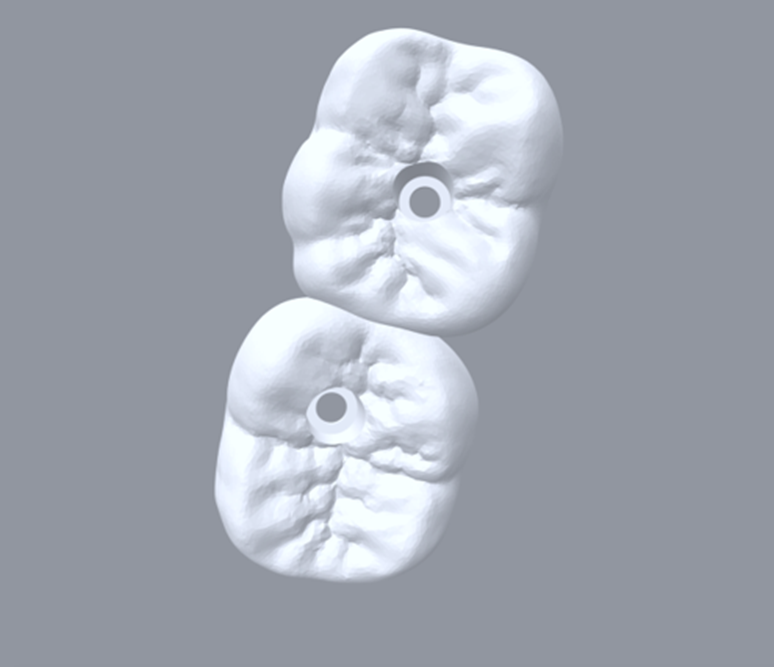

Selecionamos um caso clínico para ilustrar o fluxo de trabalho digital para Mini Cônico, onde foram planejadas duas coroas unidas nos elementos dentários 36 e 37 em zircônia monolítica, feitas sobre o pilar para próteses múltiplas.

Neste caso, a prótese múltipla foi desenhada sobre o Mini Cônico e as duas coroas foram fresadas unidas. Após a maquiagem final da zircônia monolítica, as coroas foram parafusadas sobre o Mini Cônico com um torque de 10 Ncm.

Podemos acompanhar o passo a passo das etapas, desde a seleção da altura do transmucoso do Mini Cônico até a instalação das coroas unidas no fluxo totalmente digital sem a utilização de componentes metálicos.